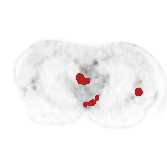

There has been growing research interest in using deep learning based method to achieve fully automated segmentation of lesion in Positron emission tomography computed tomography(PET CT) scans for the prognosis of various cancers. Recent advances in the medical image segmentation shows the nnUNET is feasible for diverse tasks. However, lesion segmentation in the PET images is not straightforward, because lesion and physiological uptake has similar distribution patterns. The Distinction of them requires extra structural information in the CT images. The present paper introduces a nnUNet based method for the lesion segmentation task. The proposed model is designed on the basis of the joint 2D and 3D nnUNET architecture to predict lesions across the whole body. It allows for automated segmentation of potential lesions. We evaluate the proposed method in the context of AutoPet Challenge, which measures the lesion segmentation performance in the metrics of dice score, false-positive volume and false-negative volume.